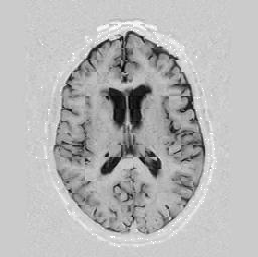

Lastly, Figure [*] shows 10 iterations at level 2, 6 iterations at level 1, and 6 at level 0.

Figure: Multi-scale NRR. From left to right, top then bottom: before NRR; after 10 iterations of NRR at level 2; after another 6 iterations of NRR at level 1; after 6 more iterations at level 0.